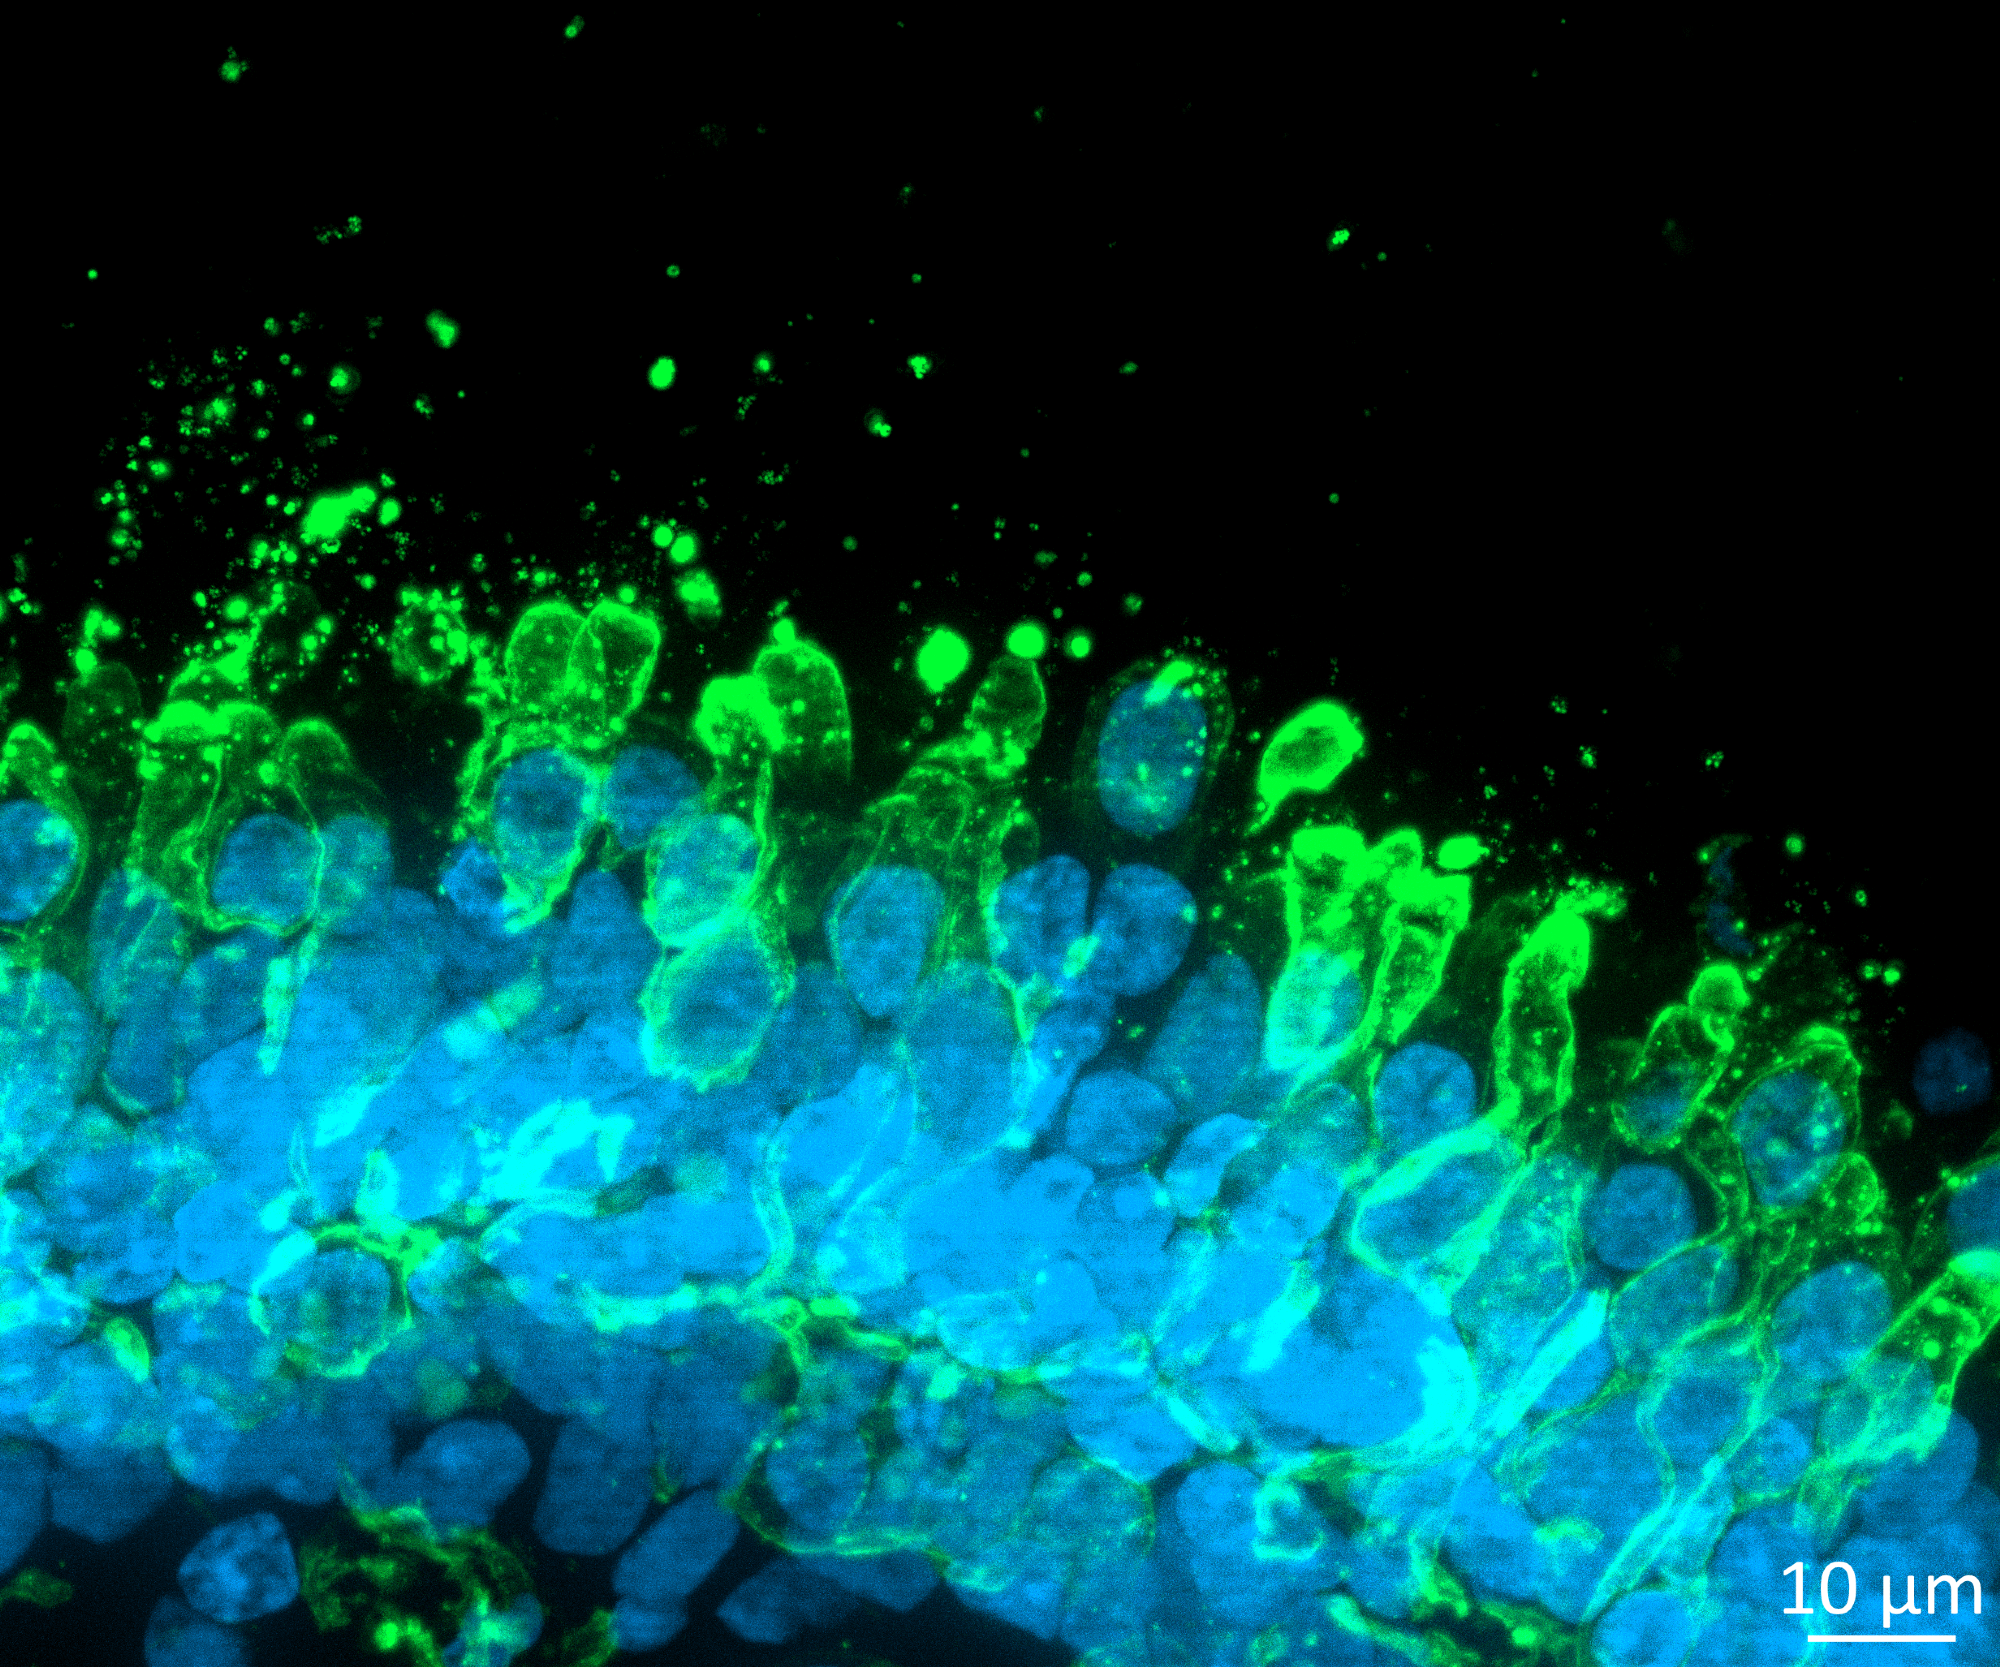

קרדיט תמונה: Newcells

ניוסלס ביוטק מפתחת בַּמַבחֵנָה מבחנים מבוססי תאים לגילוי ופיתוח תרופות וכימיקלים.

תוך שימוש במומחיות שלנו בתאי גזע פלוריפוטנטיים (iPSCs), פיזיולוגיה תאית וטכנולוגיה אורגנואידית, אנו בונים מודלים המשלבים את "הביולוגיה הטובה ביותר" לחיזוי in vivo התנהגות של תרופות חדשות.

המומחים שלנו פיתחו והשיקו מבחני למדידת תפקוד, בטיחות ויעילות של טרנספורטר במגוון סוגי תאים ורקמות, כולל כליות, רשתית וריאות.

יש לנו את היכולת לפתח וליישם פרוטוקולים למדידת תדירות פעימות ריסים ורעילות על מודל תאי אפיתל קטנים בדרכי הנשימה, רעילות רשתית ומודלים של מחלות על אורגנואידים ברשתית ואפיתל הרשתית, כמו גם הובלת תרופות בכליות, DDI ורעילות נפרו-טוקסית בבני אדם מגוון מינים פרה-קליניים.